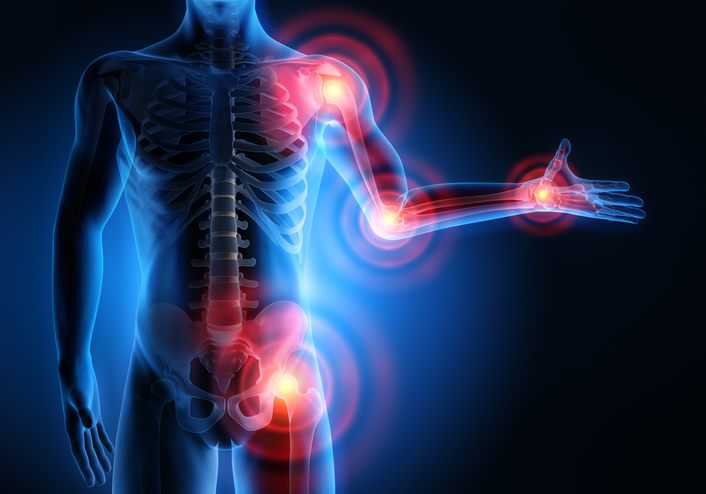

Obsah: Čo spôsobuje bolesť kĺbov bez zápalu? Prečo ma zrazu bolia kĺby? Viacnásobná bolesť kĺbo...

Obsah: Súvislosť medzi ulceróznou kolitídou a bolesťou kĺbov Čo môžete urobiť, aby ste zvládli b...

Obsah: Príznaky náhlej bolesti kolena Príčiny náhlej bolesti kolena Liečba náhlej bolesti kolen...

Obsah: Domáce prostriedky na bolesť kolena Liečba bolesti kolena Príčiny bolesti kolena Diagno...